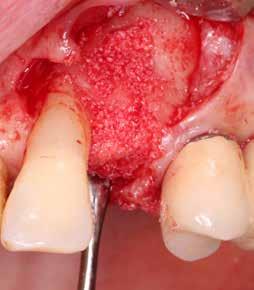

kép). A bemutatott esetben Nobel Replace CC 4,3x13mm implantátumot helyeztünk be, amely a bukkális oldalon direkt kontaktusba került a megmaradt foggyökérdarabbal (7. kép). Az alveolus oldalfalai és a körszimmetrikius implantátum közötti hézag kitöltésére bovin eredetű xenograftot (Creos S xenogain) használtunk (8. kép). A hasonló

6. kép: Implantátum-ágy preparáció. 7. a–b. képek: Implantátum behelyezés. 8. kép: A behelyezett implantátum. 10. a–b képek: Azonnali ideiglenes korona készítése. 9. kép: Megfelelő primer stabilitás.